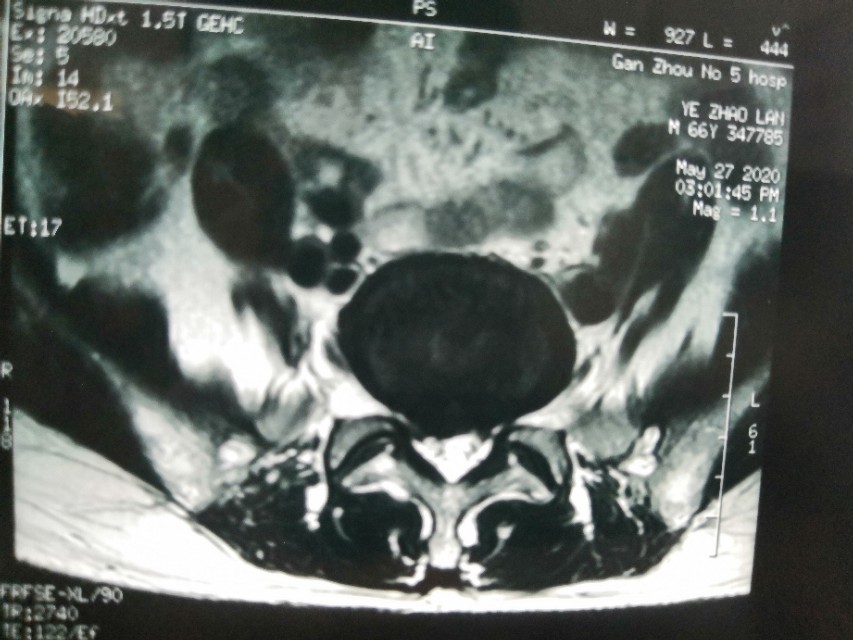

现在分享一个腰椎间盘突出症的患者的经典病例!老年患者叶某,女性,66岁,反复腰痛伴右下肢放射痛3月,加重2天!如图所示:

从影像学检查可以看出患者L5/S1椎间盘向右后方突出约7.2mm,同层伴有椎管狭窄!